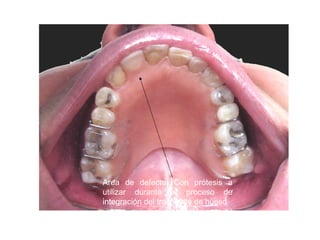

Area de defecto. Con prótesis a

utilizar durante el proceso de

integración del trasplante de hueso

Area de defecto.Con prótesis a utilizar durante el proceso de integración del trasplante de hueso